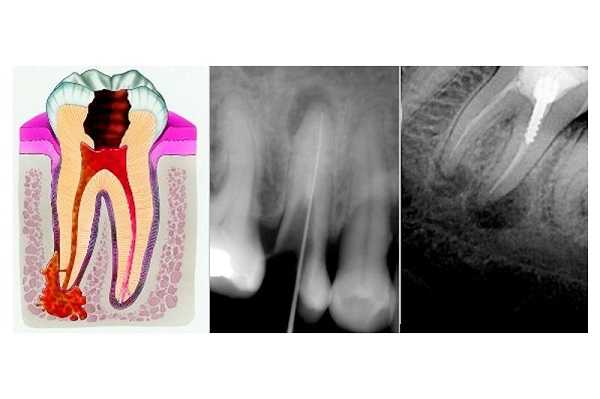

Апикальный периодонтит - это воспаление соединительнотканного комплекса, образующего зубодесневую связку (периодонт), локализующееся вокруг верхушки корня. В острой форме апикальный периодонтит проявляет себя болью и отеком в области поражения, реакцией на горячее, высокой температурой тела и общим недомоганием. Диагностируется апикальный периодонтит во время стоматологического осмотра на основании анамнеза, выявленных клинических проявлений и рентгенологического исследования. Лечение апикального периодонтита заключается в препарировании зуба, обработке каналов, применении противовоспалительных и антибактериальных препаратов, проведении физиотерапии и последующем пломбировании каналов и коронки зуба.

Апикальный (верхушечный) периодонтит - поражение тканей зубодесневой связки, при котором вокруг верхушки корня образуется очаг воспаления и происходит последующая постепенная деструкция периодонта. Это наиболее часто встречающаяся в терапевтической стоматологии форма периодонтита: ее диагностируют примерно у 30% пациентов в возрасте 21-60 лет. Чаще всего апикальный периодонтит является осложнением пульпита. Заболевание опасно своими последствиями - в случае отсутствия своевременного лечения апикальный периодонтит может переходить в хроническую форму, чреватую образованием гранулем, кист и свищей, а также осложняться периоститом, околочелюстным абсцессом, флегмоной, остеомиелитом челюсти и сепсисом. Развитие апикального периодонтита особенно опасно во время беременности.

- Рентгенография зуба. В случае хронического гранулирующего периодонтита в апикальной области обнаруживается участок разрежения костной ткани с нечеткими границами размерами от 1 до 8 мм. Хронический гранулематозный периодонтит характеризуется ясно очерченными округлыми контурами области разрушения костной структуры вокруг верхушки корня зуба. Хронический фиброзный периодонтит на рентгенограмме проявляет себя расширенным периодонтальным пространством в апикальной области при отсутствии резорбции костной стенки альвеолы.

Самый верный способ узнать о наличии недуга или подтвердить диагноз - сделать рентгеновский снимок. По нему стоматолог не только обнаружит воспаление, но и поймет, с какой именно формой он имеет дело в конкретном случае.